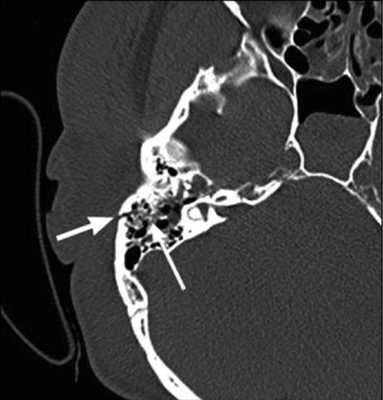

![На КТ-снимке виден перелом пирамиды височной кости (указан стрелками)]()

На КТ-снимке виден перелом пирамиды височной кости (указан стрелками)

Компьютерная томография является оптимальным вариантом для исследования костей, в том числе черепа. Костная ткань хорошо поглощает рентгеновские лучи, в результате получают четкие ее изображения. Данный метод незаменим в диагностике скрытых переломов и трещин, он хорошо выявляет деструктивные изменения.